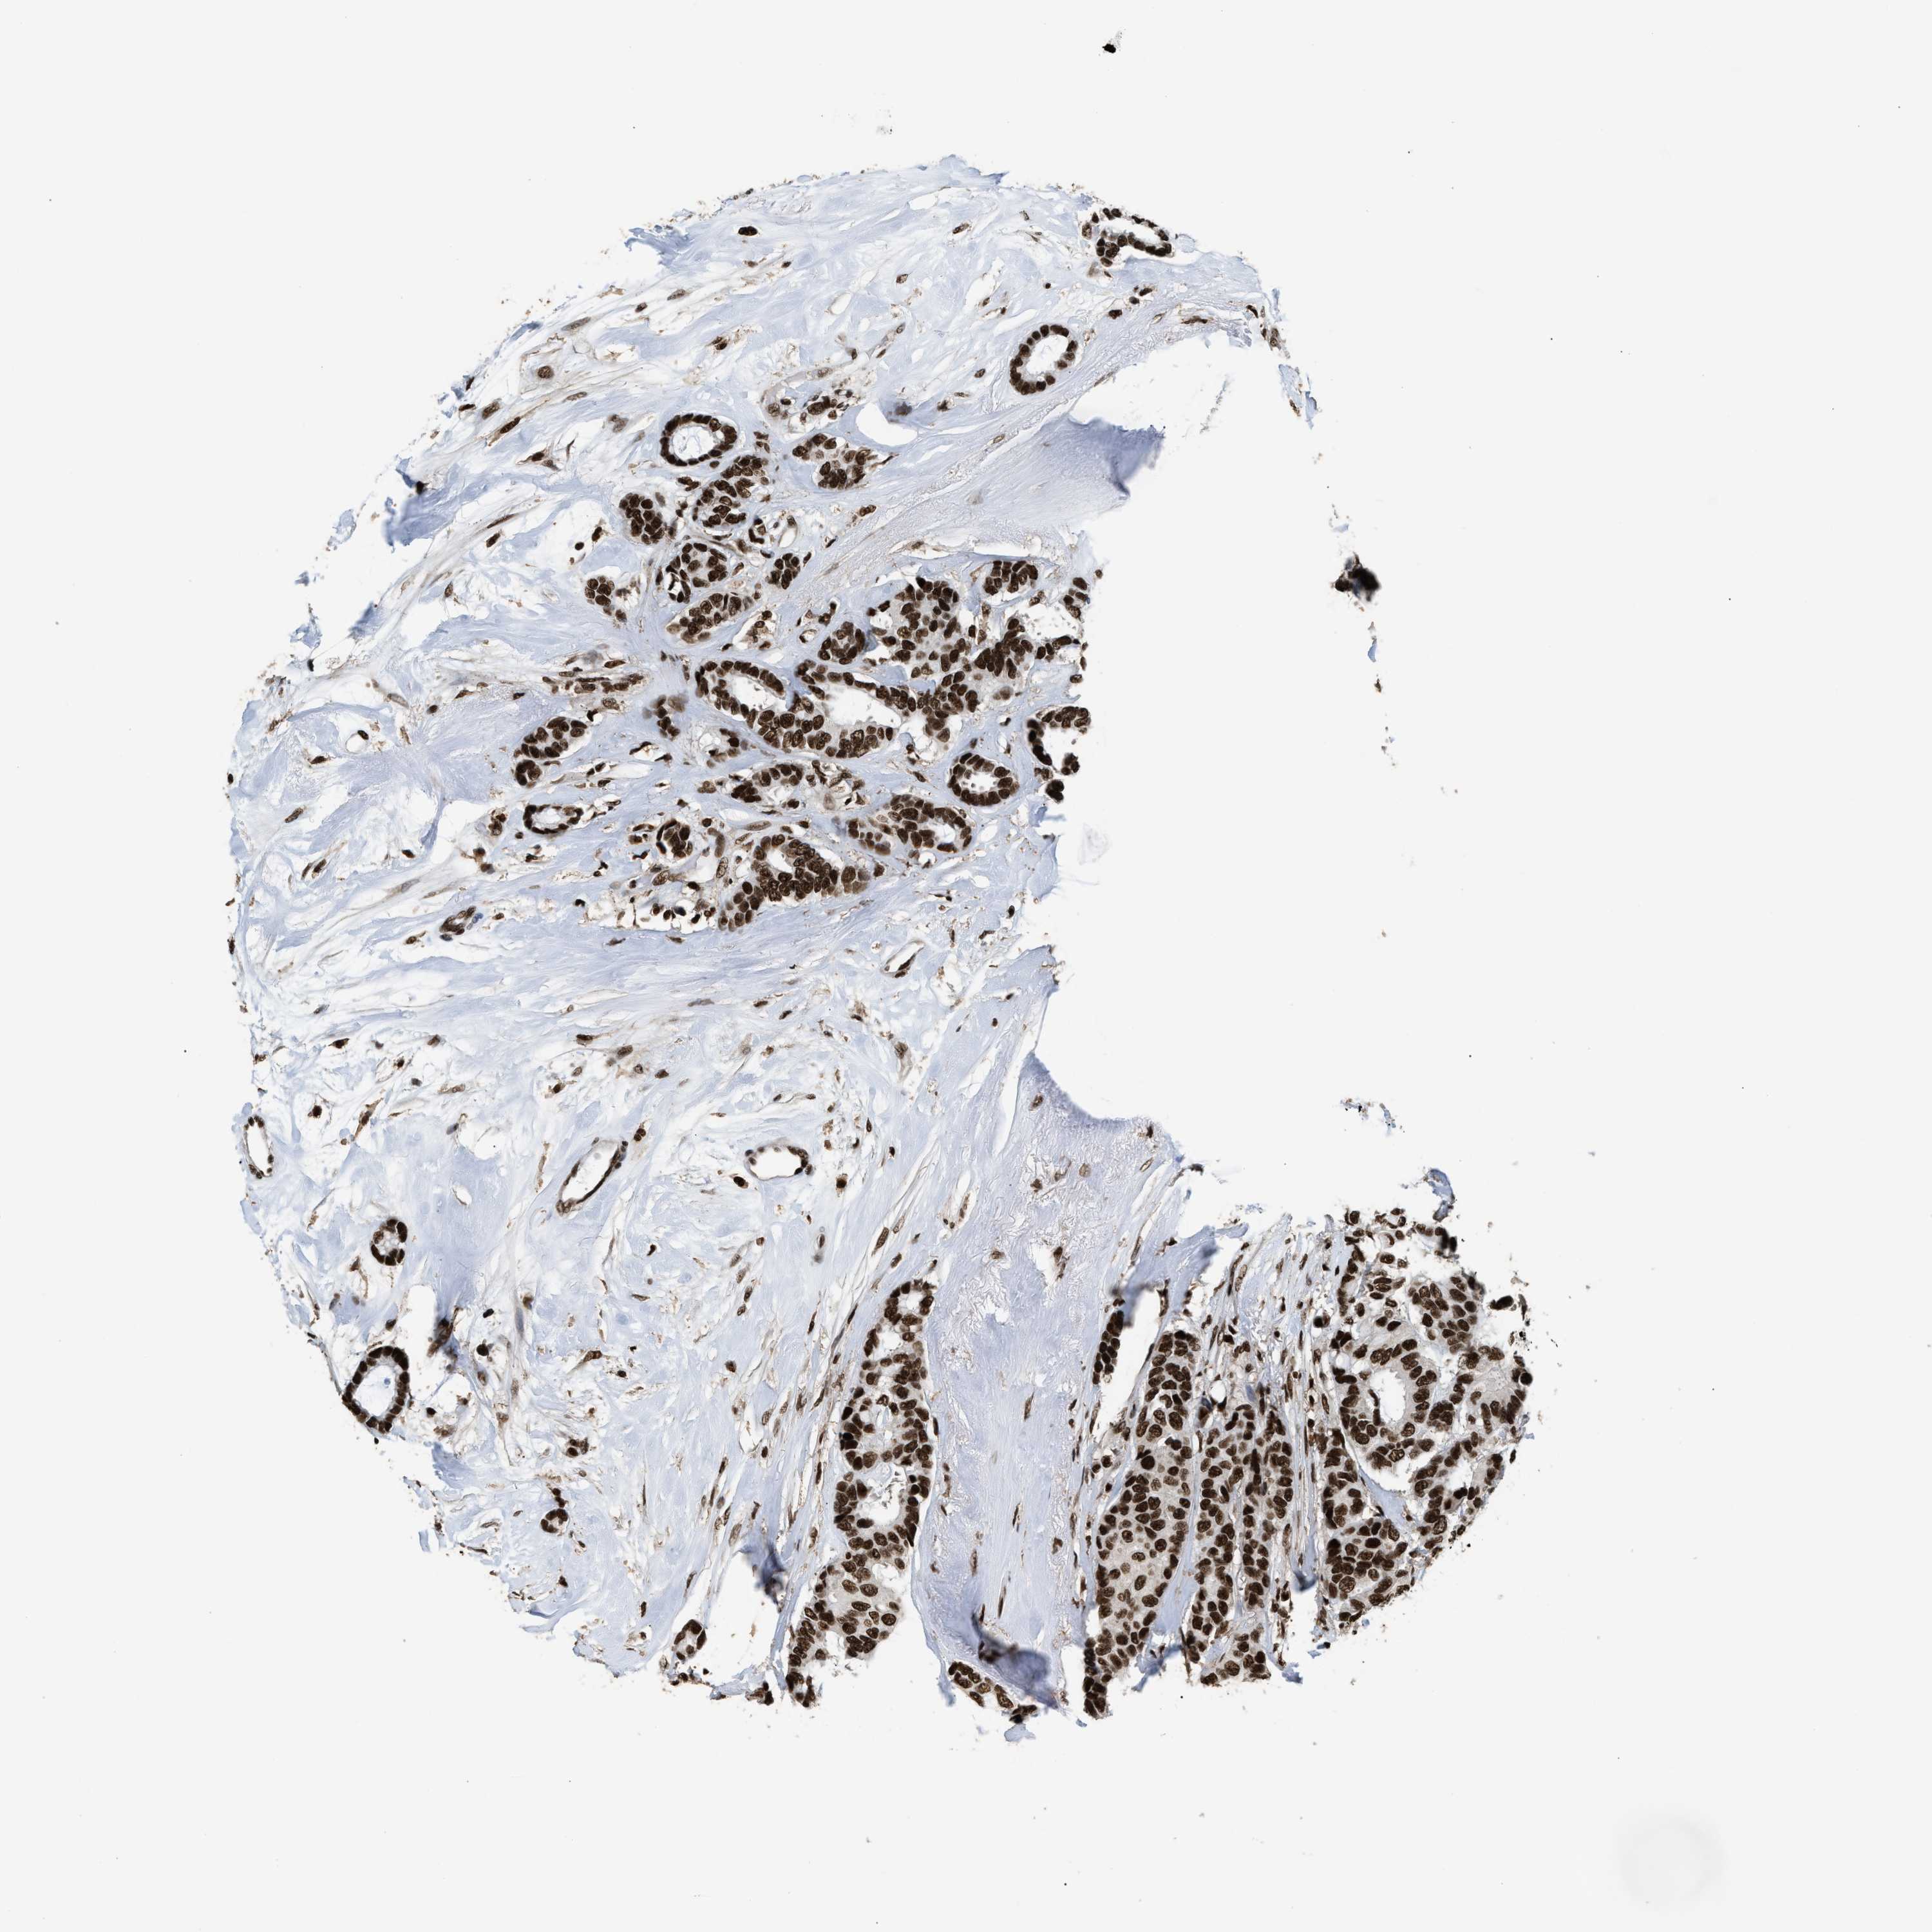

CANCER BREAST CANCER Show tissue menu

BRCA TCGA BRCA VALIDATION PROTEIN EXPRESSION

ANTIBODIES

AND

VALIDATION